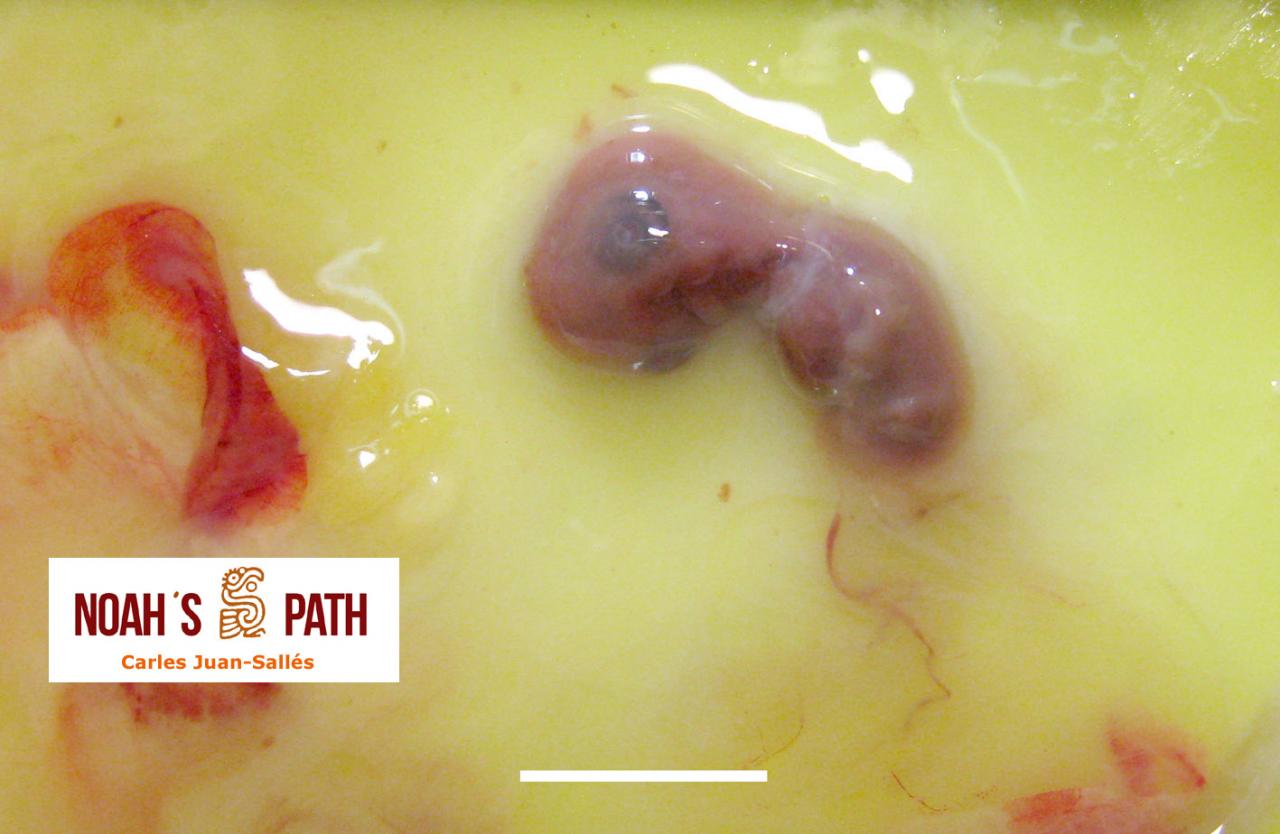

Pavo cristatus

Embrión E46 no eclosionado con malformación de saco vitelino y estrangulamiento de pata derecha

Pavo cristatus

Aspiración de fluido amniótico secundaria a malposición